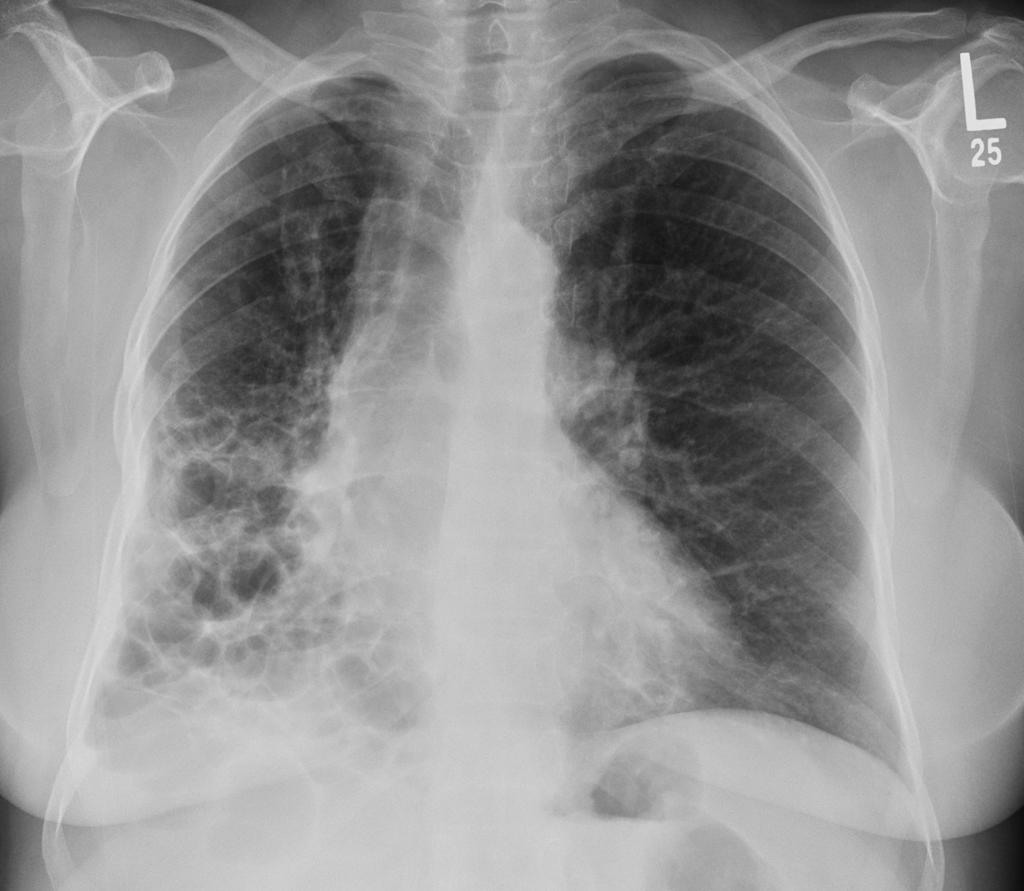

间质性肺疾病的特殊人群考虑

间质性肺疾病的特殊人群管理确实复杂,但复杂不等于无望。 每个群体都有自己的特点和需求,关键是要找到适合的方法。 老年患者需要更细致的照护,合并疾病的患者需要...